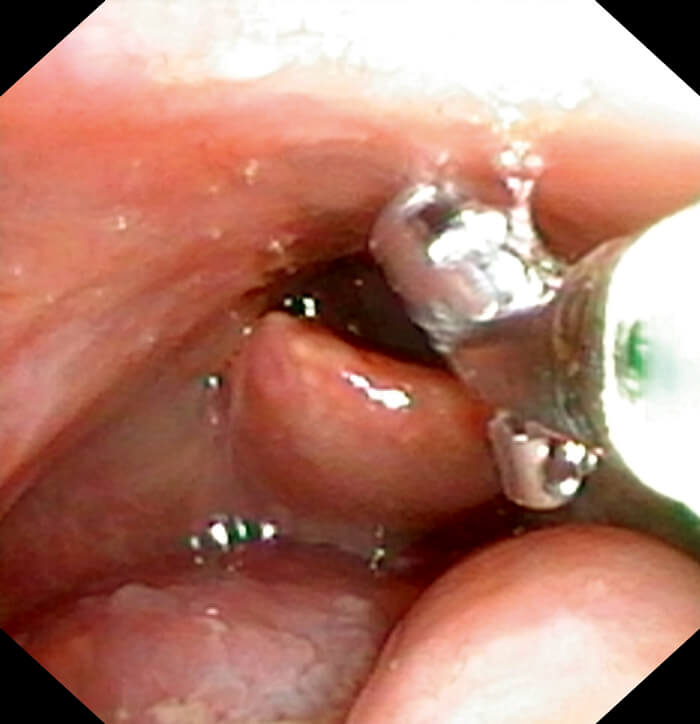

Transnasal equipment.

Transnasal biopsy.

- Biopsy forceps (EndoJawTM Alligator jaw-step fenestrated 1.9mm FB-211D, Olympus Medical Systems Corp, Japan)

The patient is instructed to make a prolonged ‘e’ sound to allow laryngeal gargling of the topical anaesthetic if the vocal folds are to be biopsied. After visualisation of the lesion, biopsies are performed using the flexible biopsy forceps (EndoJawTM Alligator jaw-step fenestrated 1.9mm FB-211D, Olympus Medical Systems Corp, Japan) which are passed down the endoscope channel. The biopsies are taken under endoscopic guidance by pushing the open jaws into the lesion, closing the jaws and pulling back swiftly on the forceps whilst holding the endoscope steady.